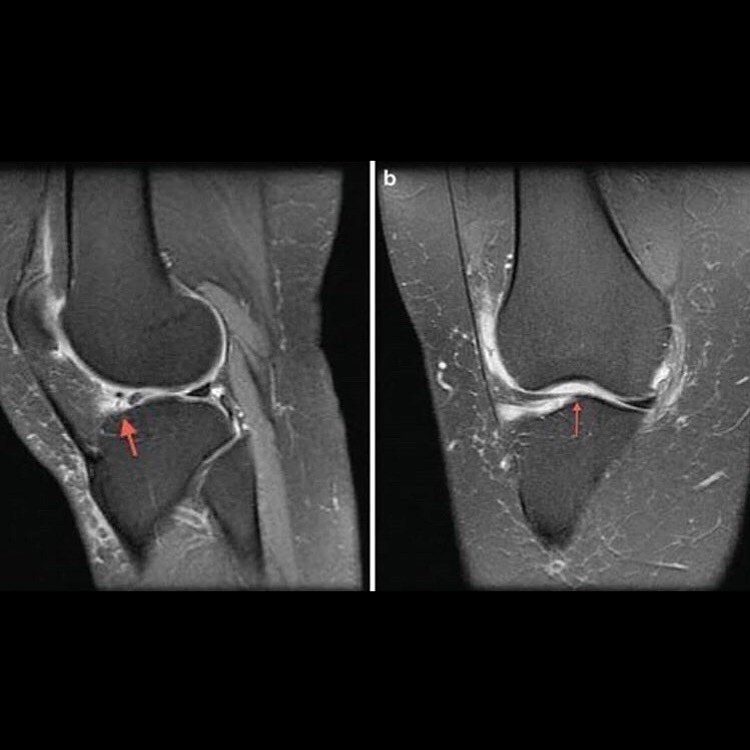

Torn Meniscus Signs & Symptoms, Test, Diagnosis, Recovery, Treatment